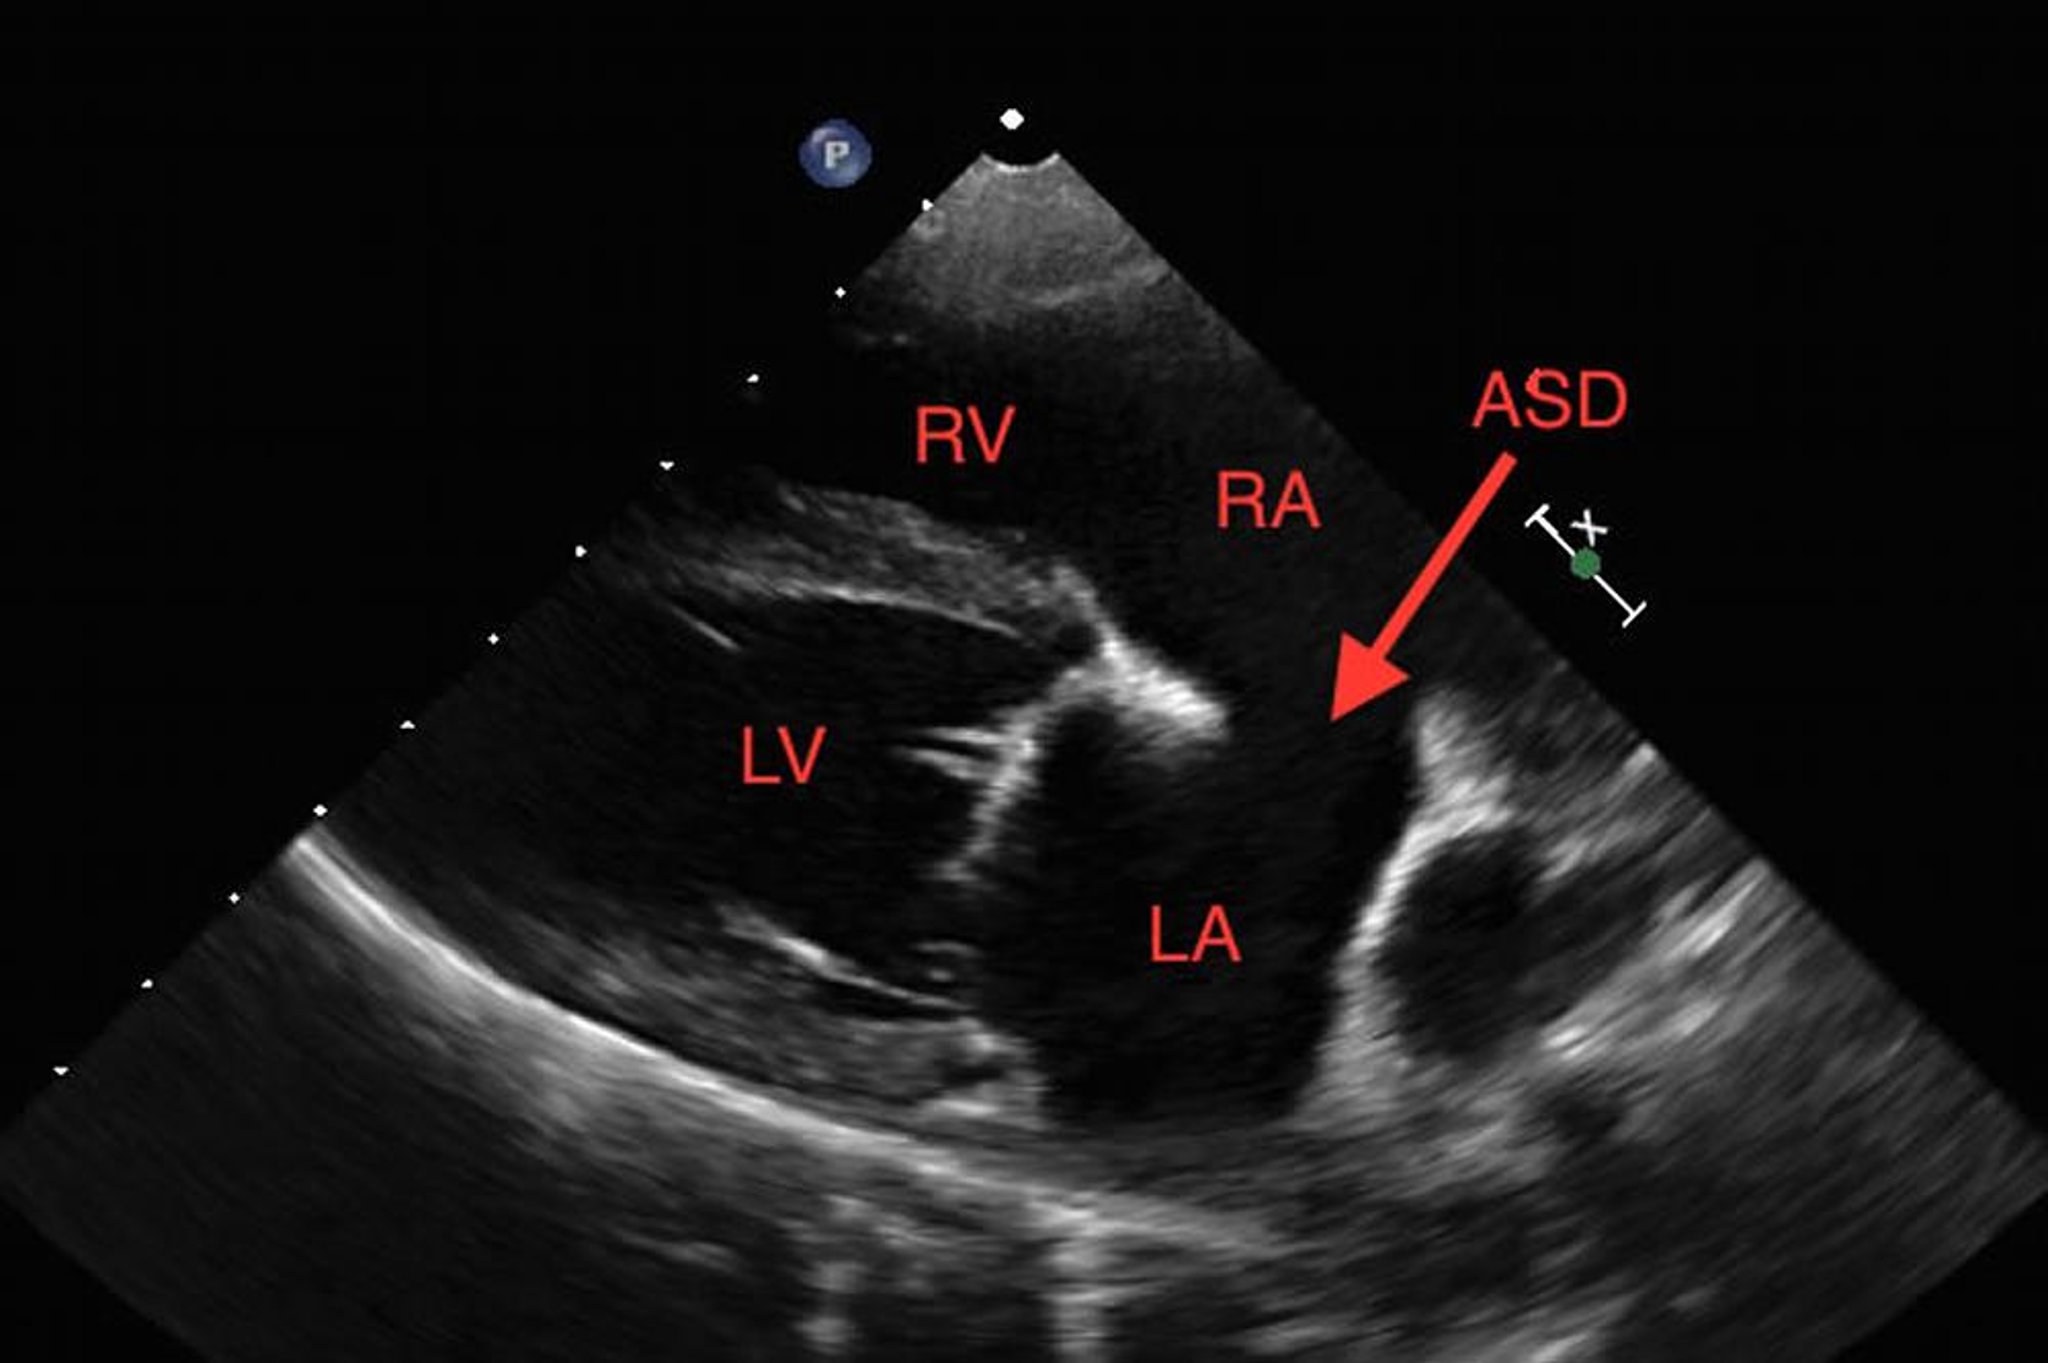

Atrial septal defect, echocardiogram, dog

Right long-axis echocardiographic view from a dog with a secundum-type atrial septal defect. ASD, atrial septal defect; LA, left atrium; LV, left ventricle; RA, right atrium; RV, right ventricle.

Courtesy of Dr. Sandra Tou.